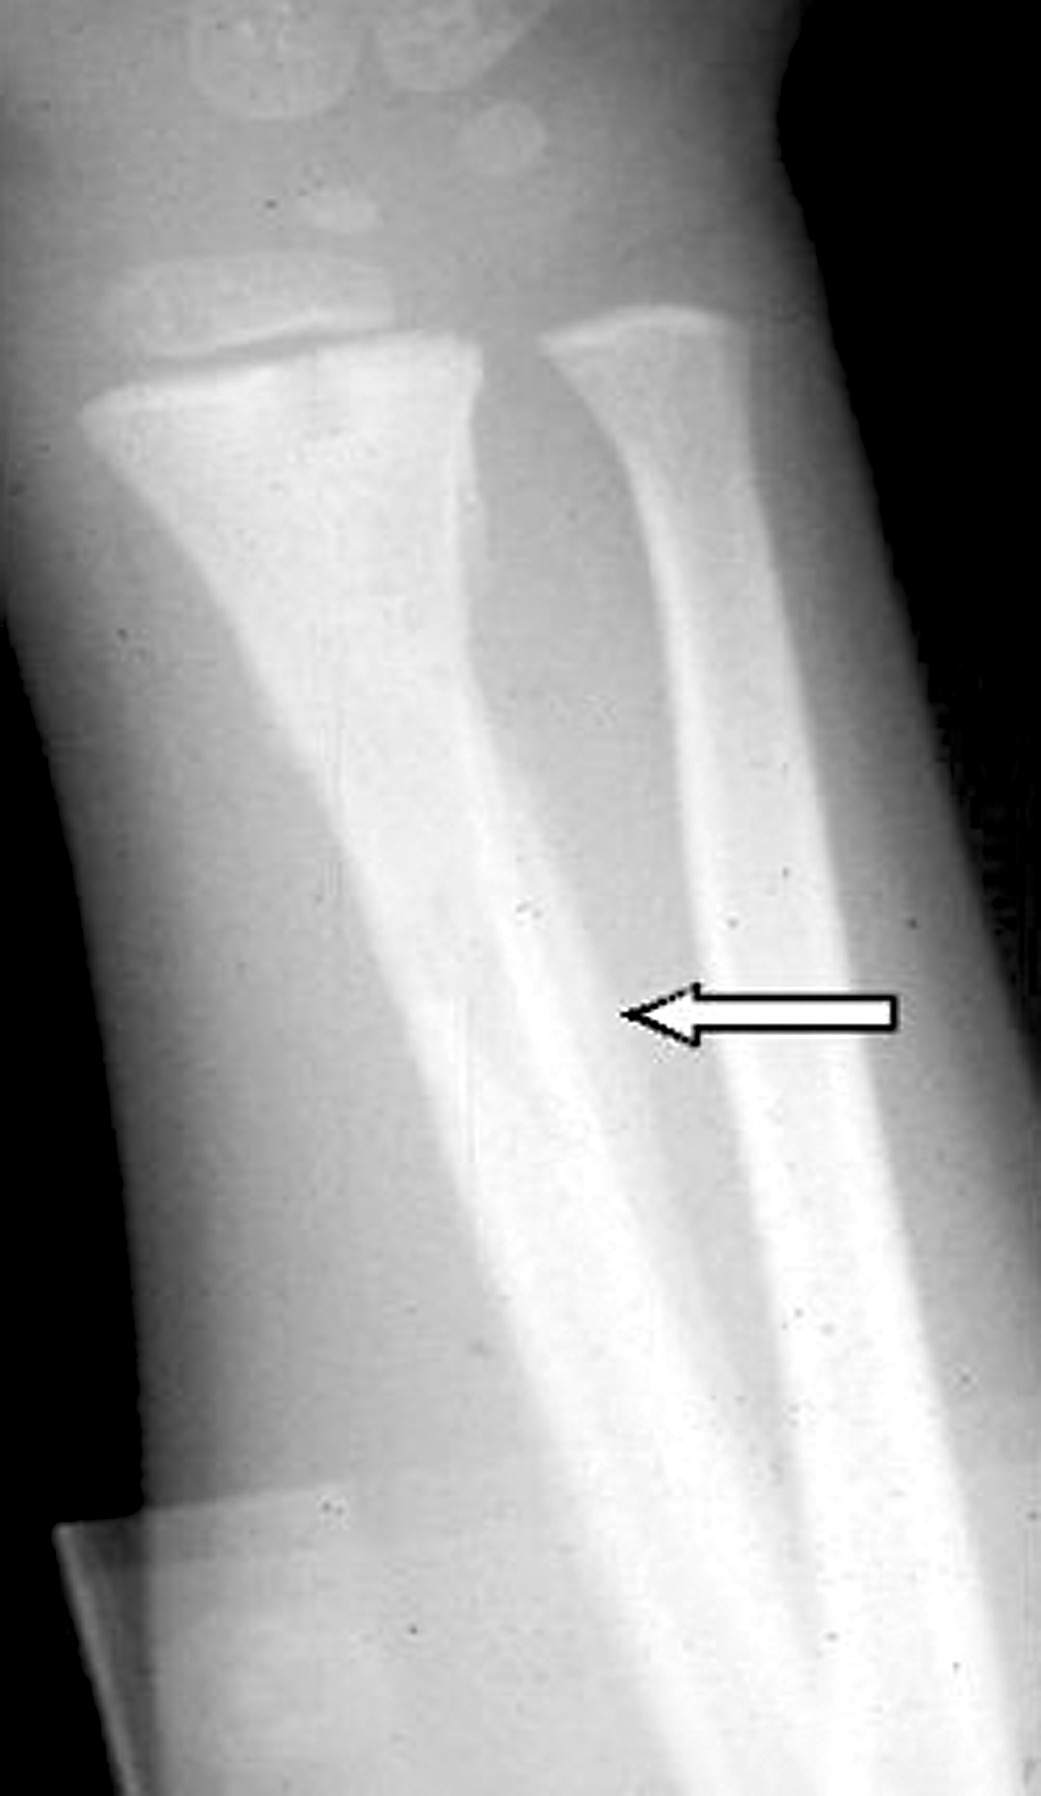

Jack-Ky Wang, MD; Laurie Meng, PA-C

Right lower leg pain prompted a 15-year-old boy to seek medical attention.